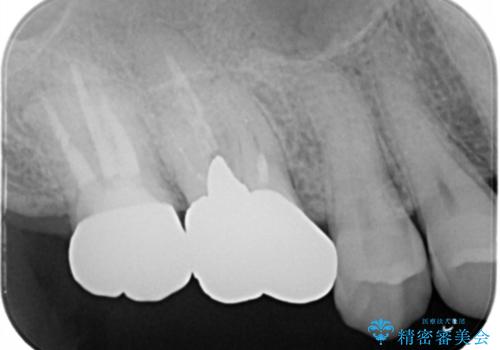

- 右上大臼歯の被せ物が取れたので作り直しを希望された患者様です。

被せ物は白くしたいとのことだったのでフルジルコニアクラウンでの治療を選択しました。

根管治療も必要だったので金属の土台を除去し、新しく土台を立て直した上で被せ物を装着しています。